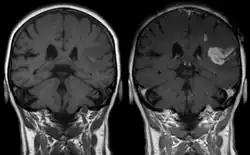

Defect of the blood–brain barrier after stroke shown in T1-weighted MRI images. Left image without, right image with contrast medium administration showing evidence of brain ischemia